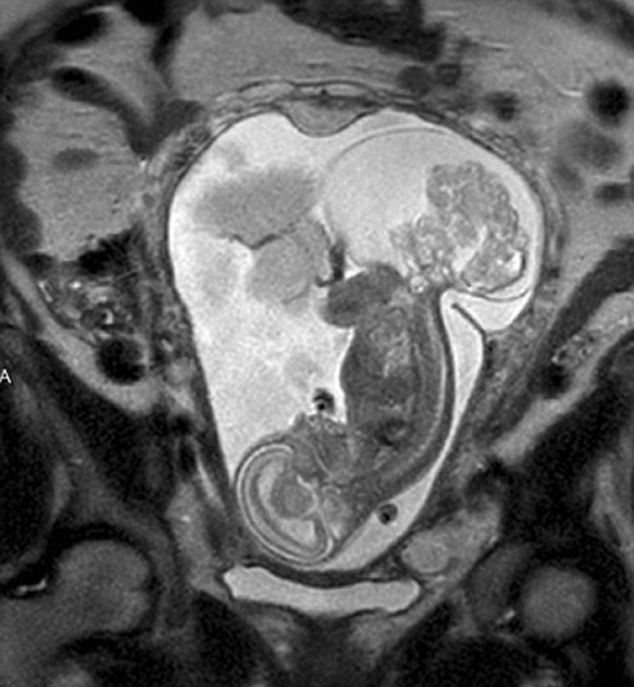

【環(huán)球網(wǎng)綜合報(bào)道】據(jù)英國(guó)《每日郵報(bào)》10月23日?qǐng)?bào)道,美國(guó)得克薩斯州布蘭諾市的女子瑪格麗特·伯默(Margaret Boemer)懷孕16周時(shí)去做產(chǎn)檢,不幸被告知胎兒尾骨上長(zhǎng)有腫瘤,她與醫(yī)生商量后決定先將胎兒取出進(jìn)行腫瘤切除手術(shù),再將其送回子宮繼續(xù)孕育。最終手術(shù)圓滿成功,12周后胎兒足月出生。

瑪格麗特稱自己當(dāng)時(shí)聽到產(chǎn)檢結(jié)果時(shí)十分害怕。“醫(yī)生說(shuō)寶寶長(zhǎng)了骶尾部畸胎瘤。我們很震驚,很害怕,因?yàn)槲覀兏静恢肋@個(gè)什么瘤到底意味著什么。”隨著時(shí)間流逝,腫瘤越來(lái)越大,胎兒滿23周時(shí)腫瘤已危及其性命。醫(yī)生告訴瑪格麗特,若想胎兒存活,只能將胎兒取出進(jìn)行手術(shù),然后再放回子宮,否則只能立即終止孕期。“這很容易做決定:讓腫瘤奪去孩子性命,或是給孩子存活的機(jī)會(huì)。我們當(dāng)然選擇后者!爆敻覃愄卣f(shuō)。

醫(yī)生將胎兒取出20分鐘后,便放回母體子宮。12周后,寶寶足月出生,敻覃愄胤Q:“這可以說(shuō)是她的第二次出生了。只要她有機(jī)會(huì)活下來(lái),我愿意承受所有風(fēng)險(xiǎn)!(實(shí)習(xí)編譯:高睿 審稿:朱盈庫(kù))